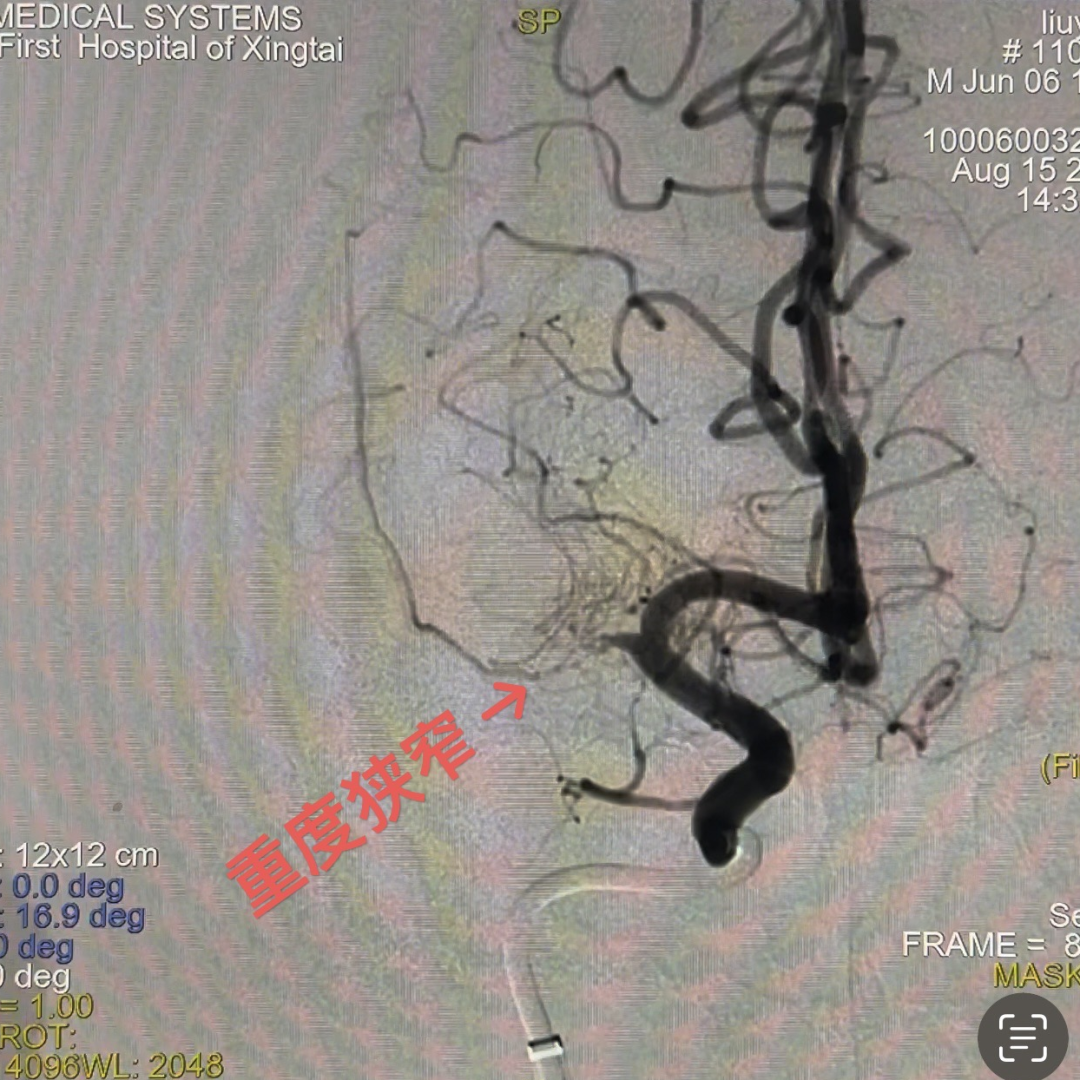

DSA提示患者右侧大脑中动脉狭窄率约95%;PWI提示右额颞顶叶低灌注。

动脉长鞘怎么置入一技之“长”丨经桡及经股困难入路应用赛诺神畅APEX TRA GC™导引导管建立通路病例合集_https://www.jmylbn.com_新闻资讯_第26张

动脉长鞘怎么置入一技之“长”丨经桡及经股困难入路应用赛诺神畅APEX TRA GC™导引导管建立通路病例合集_https://www.jmylbn.com_新闻资讯_第27张

头DWI

动脉长鞘怎么置入一技之“长”丨经桡及经股困难入路应用赛诺神畅APEX TRA GC™导引导管建立通路病例合集_https://www.jmylbn.com_新闻资讯_第31张

动脉长鞘怎么置入一技之“长”丨经桡及经股困难入路应用赛诺神畅APEX TRA GC™导引导管建立通路病例合集_https://www.jmylbn.com_新闻资讯_第32张

头PWI

DSA